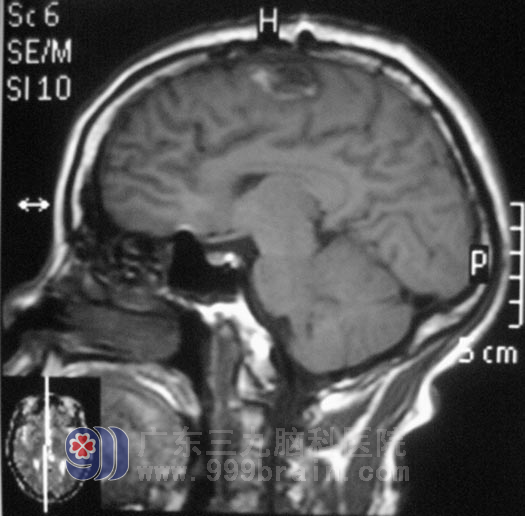

2011年12月16日,正聊着天的阿花突然出现四肢不自主抽搐摔倒在地上,持续约10分钟后自行缓解,家人将她送往当地医院,头颅CT检查结果提示:右侧额顶叶低密度影,MR检查示“右侧额顶叶异常信号影,直径约3cm,考虑胶质瘤或脑梗塞可能”。医生告知她的家人:手术可能会导致阿花瘫痪。

在广东三九脑科医院综合神经外科,鲁明主任初步考虑为胶质瘤。12月26日,鲁明主任主刀,为阿花行右侧额叶占位切除术,术中使用导航仪定位,见肿瘤位于右侧中央前回。术中唤醒麻醉结合电生理皮层电极检测及导航,手术全程让阿花在说话和肢体运动中进行。术后没有出现患者家属所担心的偏瘫情况,十天后,阿花四肢功能正常,办理出院。术后病理结果为:(右额叶)星形细胞瘤,WHO II 级。